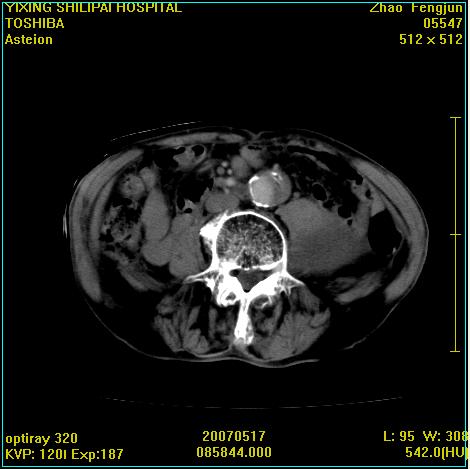

考虑:1、左侧腰大肌囊实性占位性病变(囊性神经根鞘瘤?);

2、右侧兰尾区囊性占位性病变(兰尾囊肿?囊腺癌?类癌?)

以下是引用xiaoniu在2007-5-26 10:45:00的发言:[br]腰大肌的病变应该没有问题,增强扫描还有轻度强化及细小血管影入内,应该排除脓肿,考虑占位性病变,腰大肌的占位多考虑:神经源性肿瘤。另外腹主动脉下端有真假腔的强化,考虑:主动脉夹层。[br][br][本贴已被 xiaoniu 于 2007-5-26 10:46:39 修改过]

以下是引用老爱克斯新网客在2007-5-26 18:26:00的发言:[br]1左下腹囊实性占位肿块,增强后不均匀强化,位于脊柱旁,椎体骨质无破坏软组织无肿胀,考虑神经源肿瘤神经鞘瘤可能大,2右下腹囊性占位性病变,增强后囊壁强化,考虑阑尾囊肿或囊腺瘤,